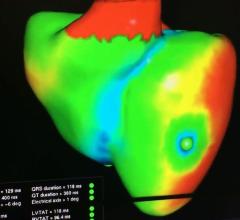

Robert Quaife, M.D., director of advanced cardiac imaging, University of Colorado Hospital, explains why advanced ...